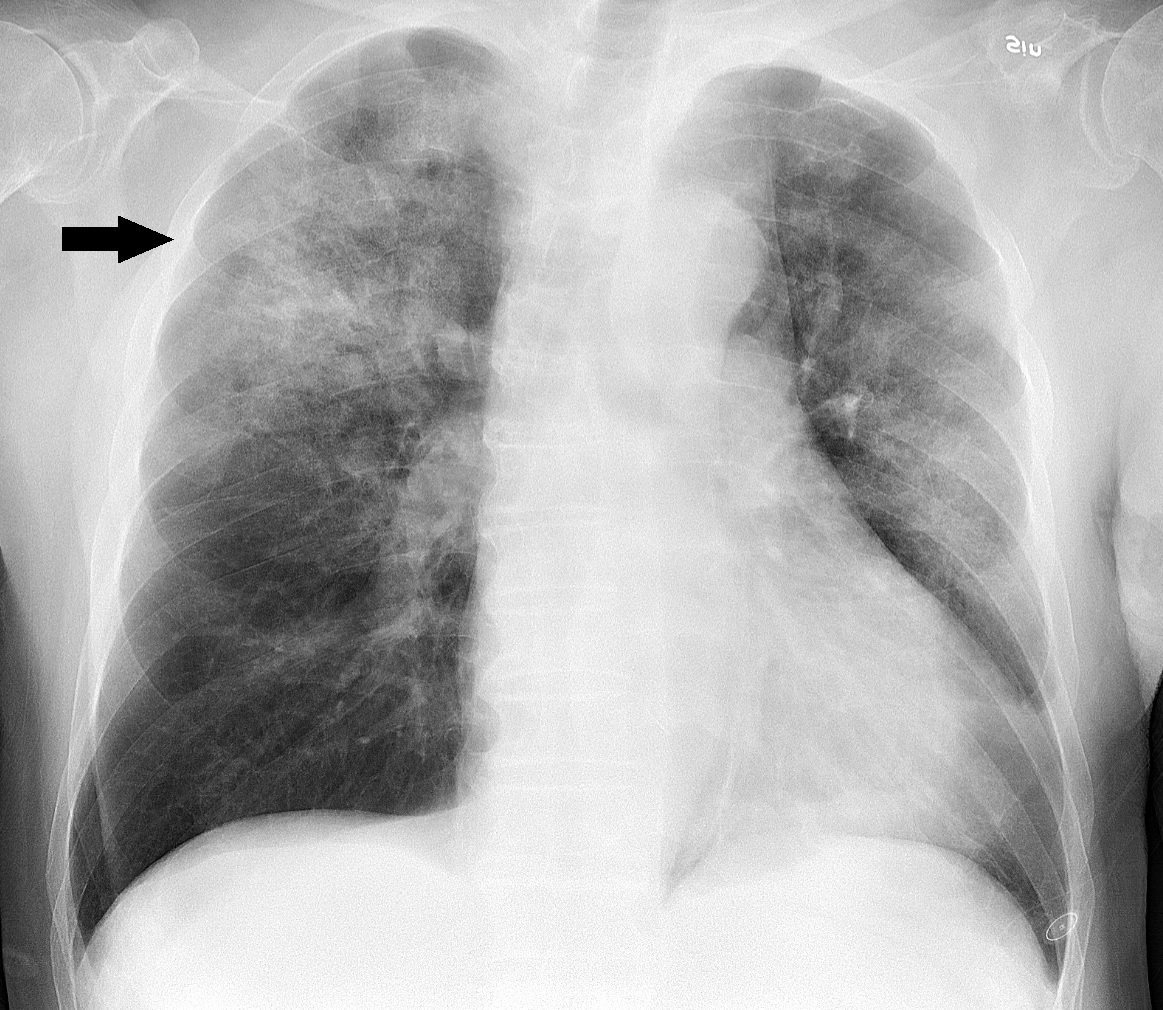

헤모필루스 인플루엔자 감염은 초기에는 상기도 감염과 유사하게 미열을 동반하며 시작된다. 며칠 내에 하기도로 진행되어 천명성 기관지염과 비슷한 양상을 보일 수 있다. 가래는 회색이나 크림색을 띠며 배출이 어렵고, 적절한 치료를 받지 않으면 기침이 몇 주 동안 지속될 수 있다. 페니실린이나 1세대 세팔로스포린에 반응하지 않는 흉부 감염을 보인 후 진단되는 경우가 많으며, 흉부 엑스선 사진에서 폐포 경화가 확인될 수 있다.[35]

침습성 ''H. influenzae'' 감염은 세균 배양, 라텍스 응집 검사, 중합효소 연쇄 반응 검사 등으로 확진한다. 비인두강이나 인후에서 배양된 ''H. influenzae''는 질병을 의미하지 않지만, 뇌척수액, 혈액, 관절액 등에서 분리된 경우는 침습성 감염을 나타낸다. 그람 염색 표본을 현미경으로 관찰하면 그람 음성 코코바실러스가 보이며, 카탈라아제 및 옥시다아제 검사에서 모두 양성 반응을 보인다. 추가적인 혈청학적 검사를 통해 캡슐 다당류를 구별하고 ''H. influenzae'' b형과 비피막 균주를 구별할 수 있다. 세균 배양은 특이적이지만 민감도가 낮아, 검체 채취 전 항생제 사용은 세균 분리율을 감소시킬 수 있다.[37]

헤모필루스 인플루엔자는 사람에게만 발생하는 질병을 일으키는 균으로, 주로 호흡기 감염과 침습성 감염을 유발한다.- 호흡기 감염: 폐렴, 중이염, 부비동염, 기관지염 등이 발생할 수 있다. 초기에는 바이러스 감염과 유사한 증상을 보이며, 며칠 내에 하기도로 진행될 수 있다. 가래 배출이 어렵고, 기침이 몇 주 동안 지속될 수 있다.[35]

- 침습성 감염: 균혈증, 폐렴, 후두개염, 급성 세균성 수막염을 유발할 수 있다.[86] 연조직염, 골수염, 감염성 관절염을 유발하기도 한다.[86] 패혈증, 수막염, 결막염, 급성 후두개염, 관절염등을 일으킨다.